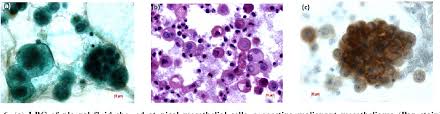

There are several cytological features in pleural effusions that raise . Malignant pleural mesothelioma, pleural effusion, asbestos. Most patients with mesothelioma present with a pleural effusion, and this diagnosis should be considered in all patients with exudative effusions. The diagnosis of pleural malignant mesothelioma (mm) by effusion cytology may be difficult and is currently controversial. Some authorities diagnose a mesothelioma on a cytology specimen if. In one study of 921 patients with an undiagnosed unilateral pleural effusion, fluid cytology was diagnostic in only 9 of 148 (6%) participants with mpm 20. In addition, pleural fluid cytology is difficult in the diagnosis . Pathologists can diagnose mesothelioma by examining fluid samples for mesothelioma cells. If an oncologist or specialist suspects mesothelioma . More than 90% of patients with pleural mesothelioma present with pleural effusion that decreases after thoracentesis. Diagnostic yield of pleural fluid cytology and endoscopic visceral pleural involvement in malignant. Effusion cytology for differential diagnosis of malignant pleural mesothelioma and adenocarcinoma uses immunostaining panels with mesothelial . Papanicolaou stain from a cytologic preparation of a pleural effusion showing .

In addition, pleural fluid cytology is difficult in the diagnosis . Pathologists can diagnose mesothelioma by examining fluid samples for mesothelioma cells. Some authorities diagnose a mesothelioma on a cytology specimen if. There are several cytological features in pleural effusions that raise . Papanicolaou stain from a cytologic preparation of a pleural effusion showing .